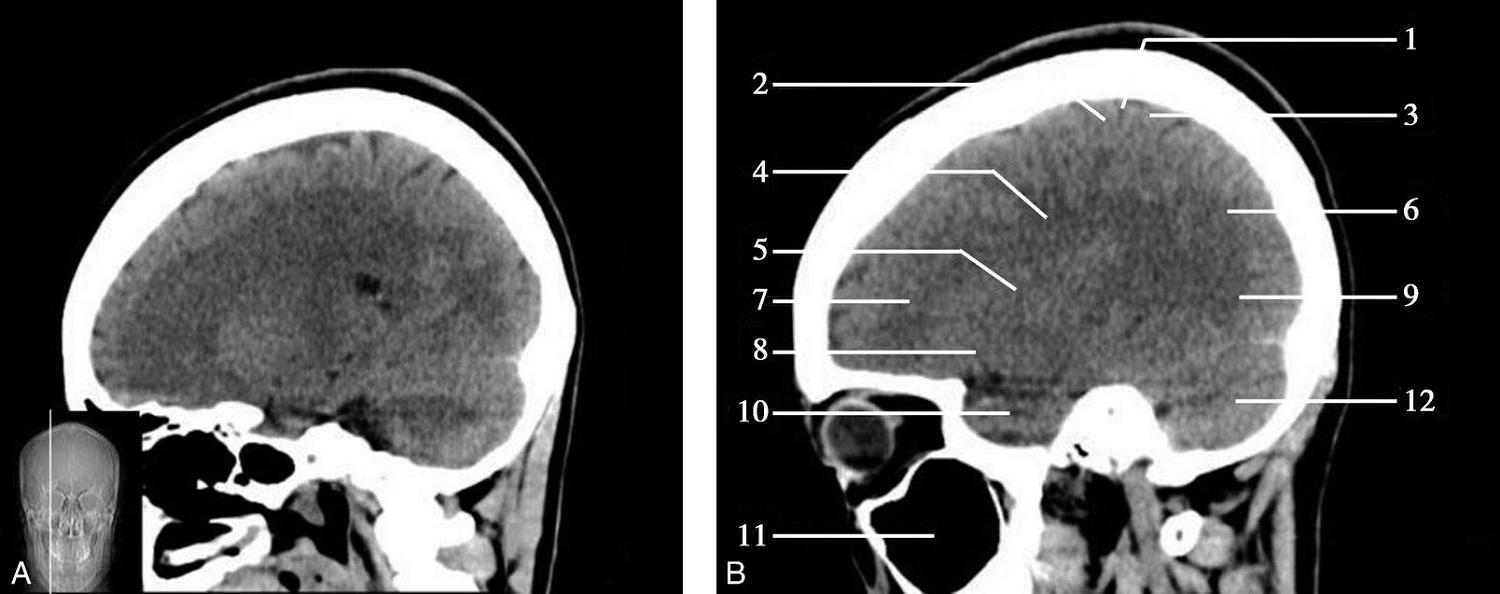

重要结构:胼胝体、垂体、中脑导水管、扣带回、中央沟、第三脑室、斜坡(图1-2-59、图1-2-60)。

图1-2-59 正中矢状面CT

A.矢状面;B.矢状面标注

1.中央沟;2.扣带回;3.胼胝体体部;4.侧脑室;5.中脑;6.胼胝体膝部;7.穹隆;8.第三脑室;9.胼胝体压部;10.垂体;11.中脑导水管;12.第四脑室;13.脑桥;14.蝶窦;15.斜坡;16.小脑扁桃体;17.延髓

图1-2-60 正中矢状面骨窗CT

1.顶骨;2.枕骨;3.斜坡;4.额骨;5.蝶鞍

此层面可显示胼胝体全貌,它位于层面中央区域,是呈上凸下凹的弧形结构,由前向后分为嘴、膝、体和压四部分。扣带回环绕胼胝体上方,扣带沟位于扣带回的上方。大脑半球中部和后部分别可见较深且恒定的中央沟和顶枕沟。中央沟为是额叶顶叶分界标志。

胼胝体下方为侧脑室及穹窿,第三脑室借穹窿与前上方的侧脑室体部分开,背侧丘脑的内侧面以及中脑顶盖分别为第三脑室的外侧壁和底。第三脑室向前籍室间孔与侧脑室相通,向下经中脑导水管通第四脑室。中脑腔狭窄呈管状,即称为中脑导水管,中脑导水管畸形,常见者为导水管的分叉畸形和狭窄,其次可见中脑导水管膈膜,造成先天性脑积水。

脑干由中脑、脑桥和延髓组成,自第三脑室底向下后稍斜行,移行于颈髓。由上至下,脑干腹侧可见脚间池、桥前池和延髓池,脑干背侧可见大脑大静脉池、四叠体池和小脑延髓池。

垂体位于蝶鞍内,其前部为腺垂体,后上部分为神经垂体。垂体下方为鞍底及蝶窦,上缘因鞍膈存在而平直,垂体借垂体柄向上连于丘脑下部。垂体的前上方见视交叉和视束。斜坡作为前颅窝底的重要组成部分与多个重要结构相比邻,矢状位呈三角形,颅内肿瘤或颅外鼻咽部恶性肿瘤均可侵犯至此,原发肿瘤常见为脊索瘤。小脑幕居枕叶和小脑之间,向后下连接窦汇,向前至中脑后方游离,称小脑幕切迹。小脑幕下方为小脑扁桃体。成年人小脑扁桃体下缘由枕骨大孔向下疝入椎管超过5mm称为Chiari畸形,以矢状位显示最佳。